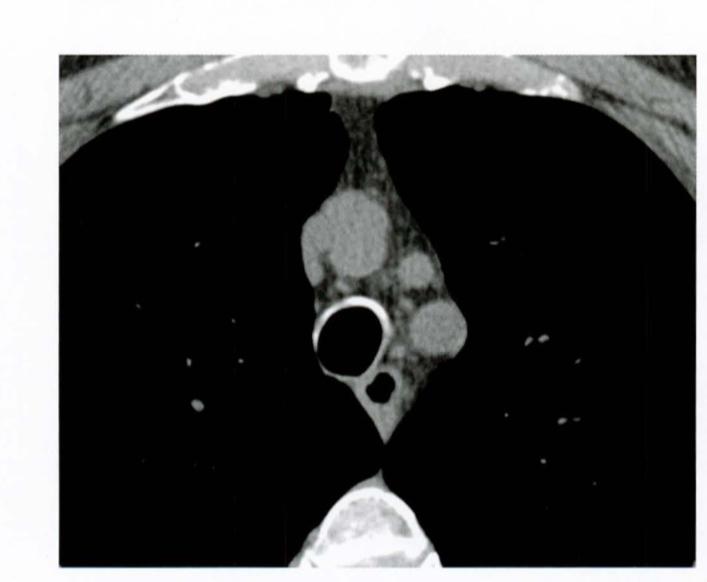

Qual a anatomia vascular básica da janela do mediastino?

Mensuração do diâmetro do tronco da artéria pulmonar